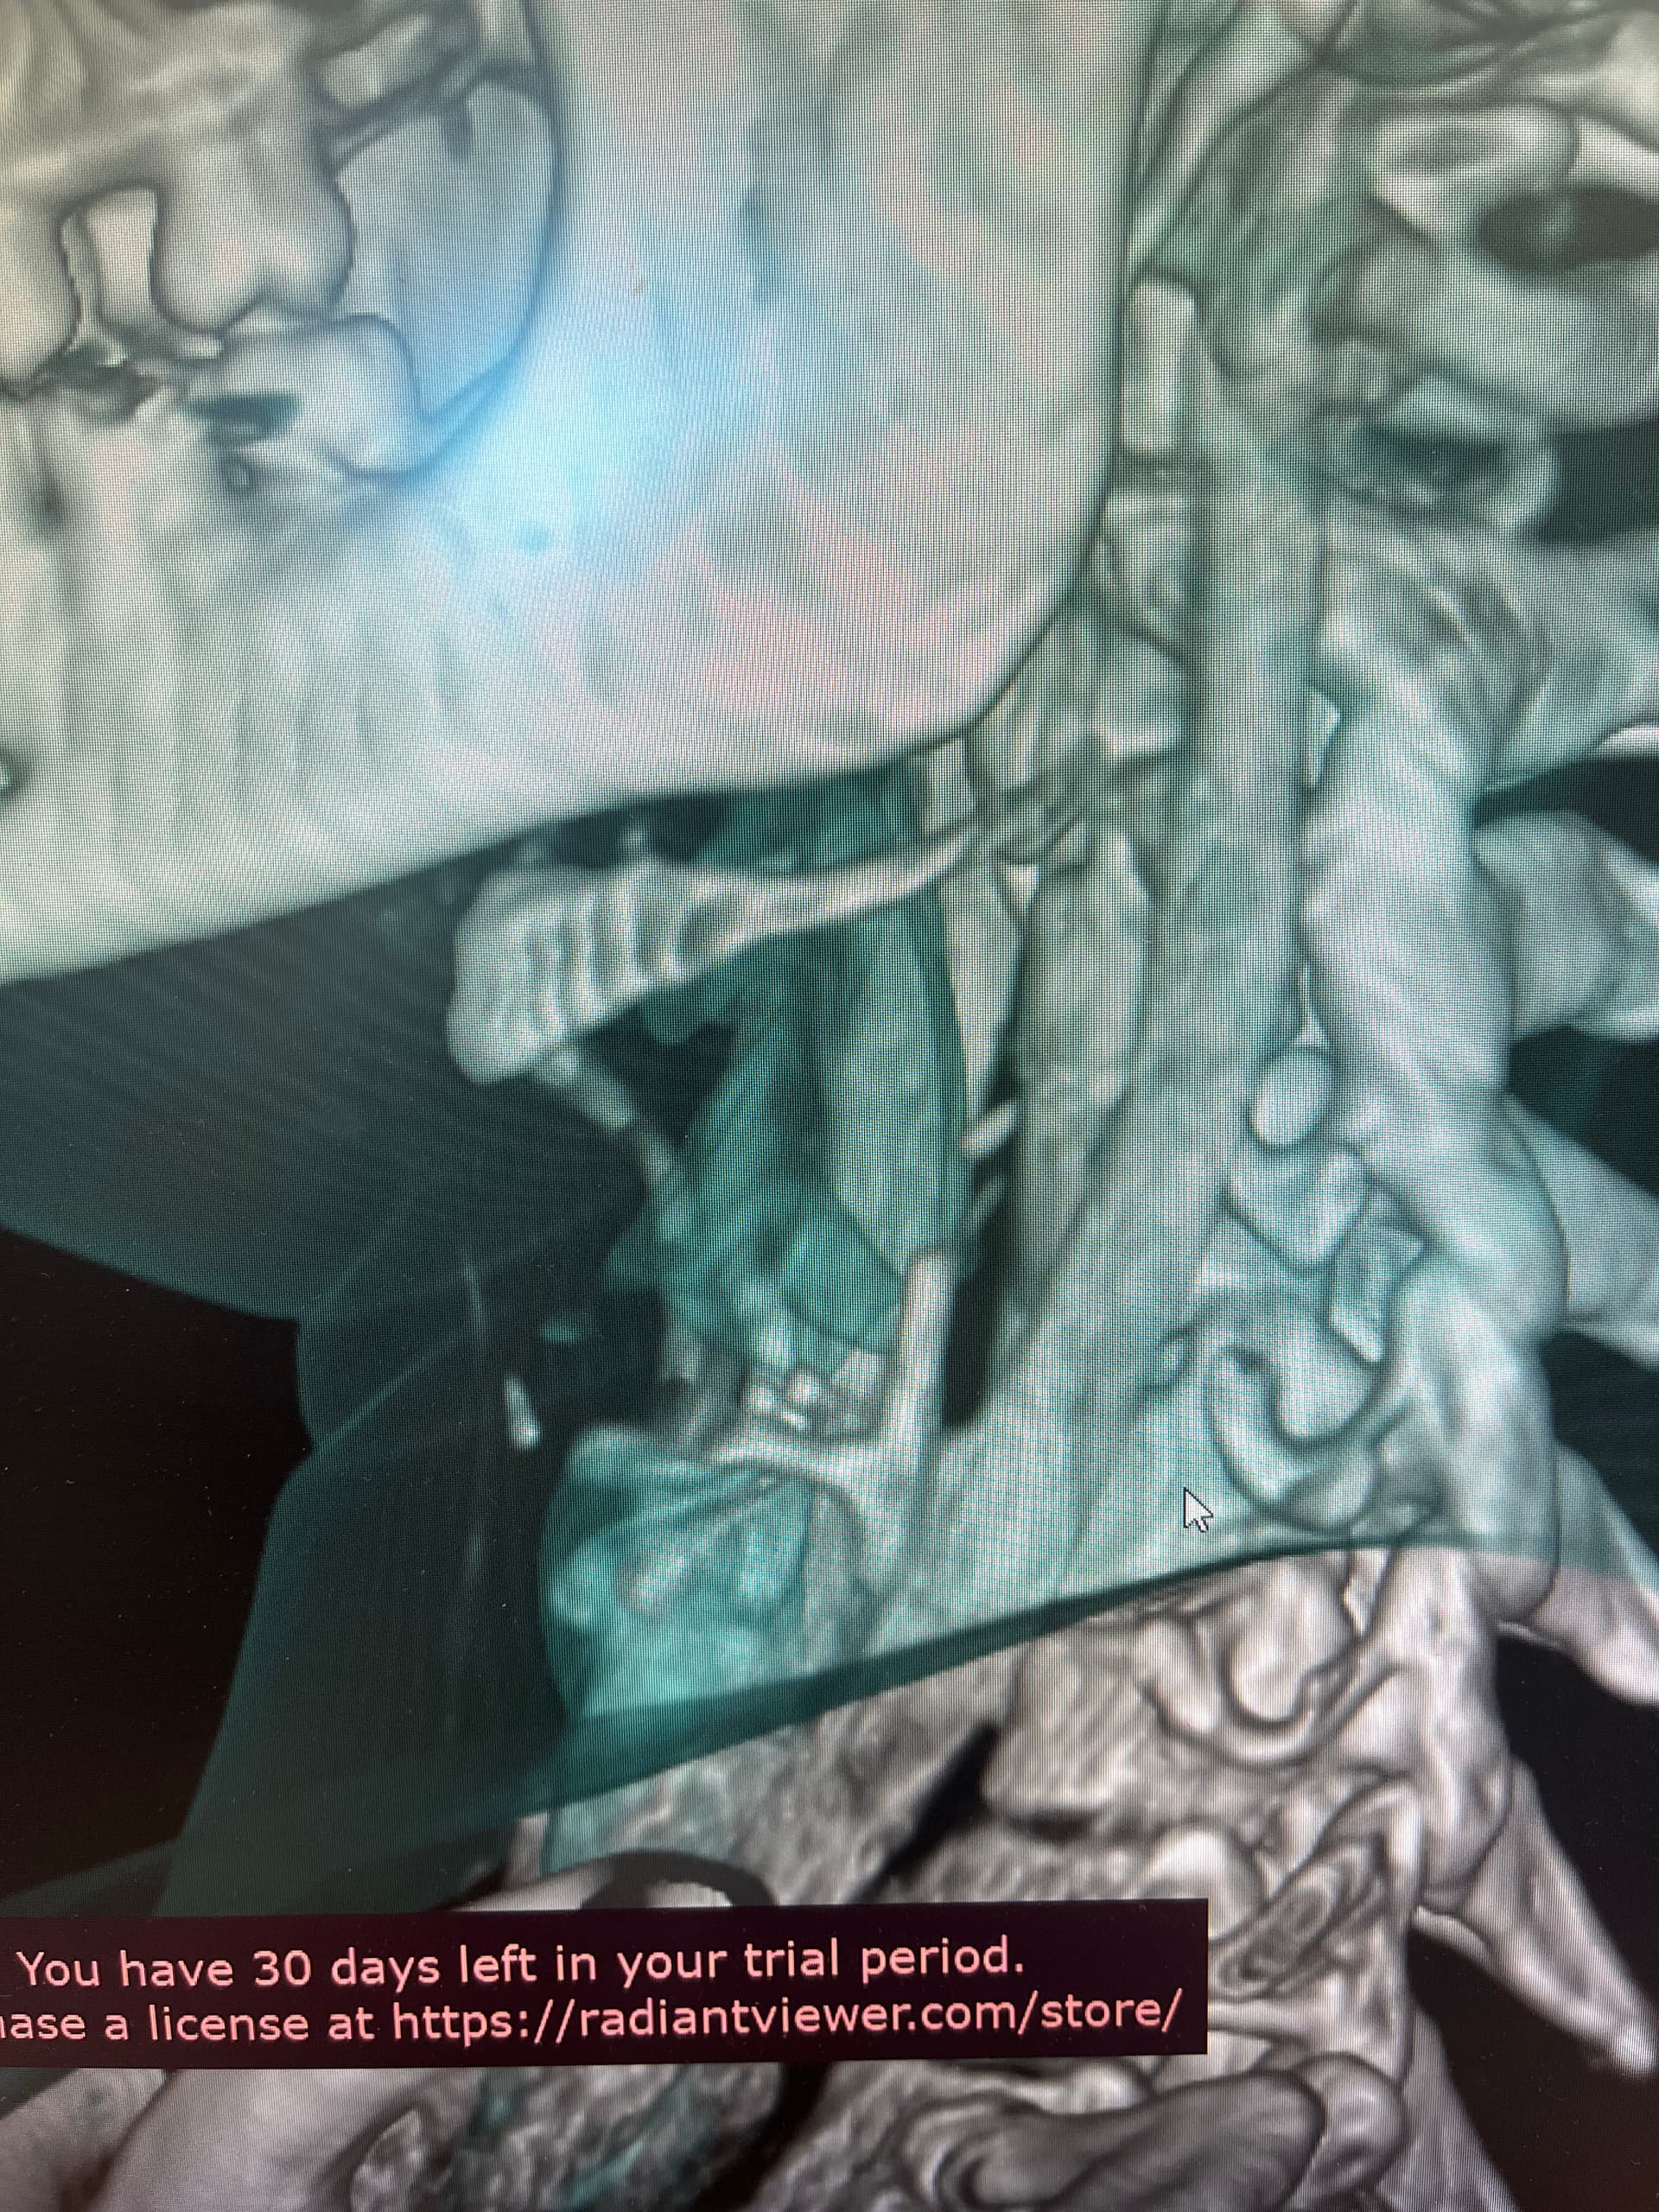

Might want to check out left styloid process and ligament also. Can see it on the 3D but not all of it due to blood vessels. Might be contributing to the hyoid injury/problem if ligament is calcified.

Good observation, @Rex!

So frustrating that you were doing well! The hyoid bone processes do look quite long & very close to your vertebrae, as the others have said, so worth looking in to if you can…